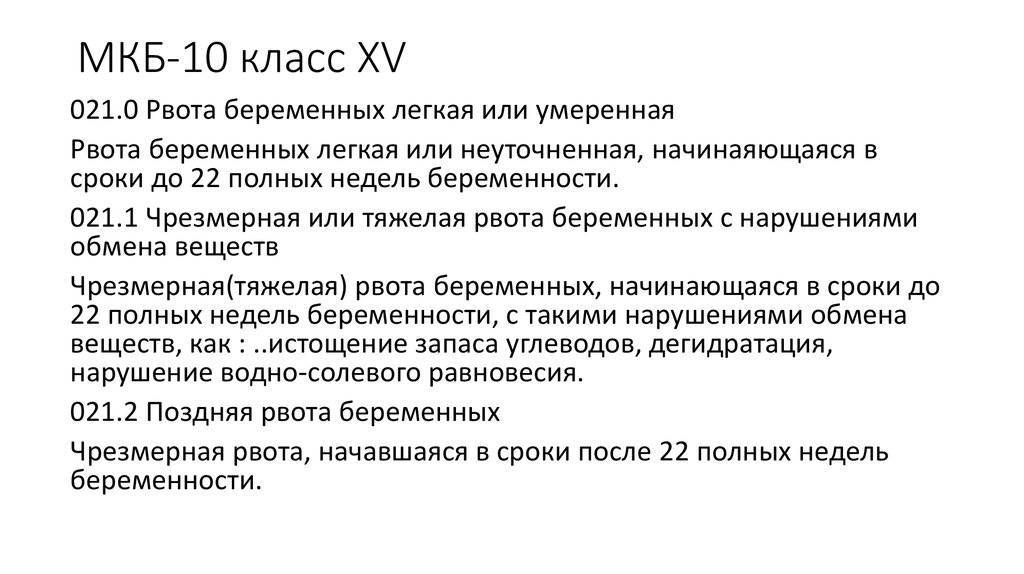

Код мкб 10 атерома головы

Код мкб 10 атерома головы 109 фото